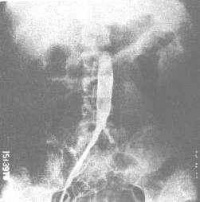

2.血管造影:

(l)管腔粗细不均、边缘比较光滑的向心性动脉狭窄和阻塞。

(2)动脉扩张动脉瘤形成。

(3)以腹主动脉、胸降主动脉、锁骨下动脉肾动脉为其好发部位。主动脉分支病变多累及开口部或近心段,局限性狭窄、阻塞多见。侵犯主动脉的狭窄,病变多较广泛。

(4)本病常为多发病变,可表现为不同组合。

(2)血管造影检查 ①数字减影血管造影(DSA) 是一种数字图像处理系统,为一项较好的筛选方法,本法优点为操作 简便易行,检查时间短,对病人负担小,反差分辨率高,对低反差区域病变也可显示。对头颅部动脉,颈动脉,胸腹主动脉,肾动脉,四肢动脉,肺动脉及心腔等均可进行造影,对大动脉炎的诊断价值较大,一般可代替肾动脉造影,本法缺点是对脏器内小动脉,如肾内小动脉分支显示不清,必要时仍需进行选择性动脉造影。 ②动脉造影 可直接显示受累血管管腔变化,管径的大小,管壁是否光滑,影响血管的范围和受累血管的长度。